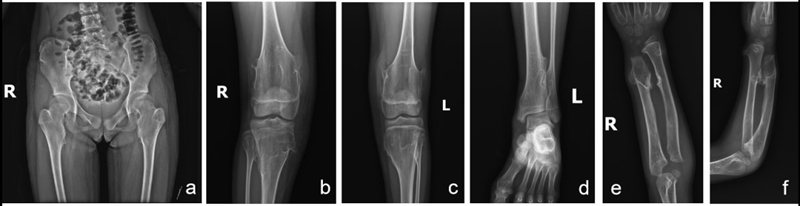

HME通常在童龄发病,外生骨疣可表现为多节、坚硬和皮下隆起。通常同时累及上肢和下肢5-6处关节周围,患者当中70%会累及股骨远端,70%累及胫骨近端,30%累及腓骨近端,膝关节周围受累的发生率为94%。此外,累及近端肱骨、肩胛骨、肋骨、指骨、远端胫骨和足部骨骼的发生率依次降低[1](图1)。通过患者特异性的皮下隆起外观可做出诊断。随着病程进展,四肢相对躯干发生非比例性地生长延迟。10%的患者有下肢不等长,到生长高峰期此差异性会更加明显。当这类患者的骨骼生长受累时,同时伴有骨软骨瘤的出现,研究发现,骨软骨瘤的大小与骨骼长度呈反比例关系,表明骨骼的生长障碍可能是由于骨软骨瘤的增大,而非骨骼发育不良所导致的[7]。

图1. HME患者的X线片表现为全身多发性外生骨疣。好发部位包括股骨近端(a),膝关节周围(b、c),踝关节周围(d)和尺桡骨远端(e、f)